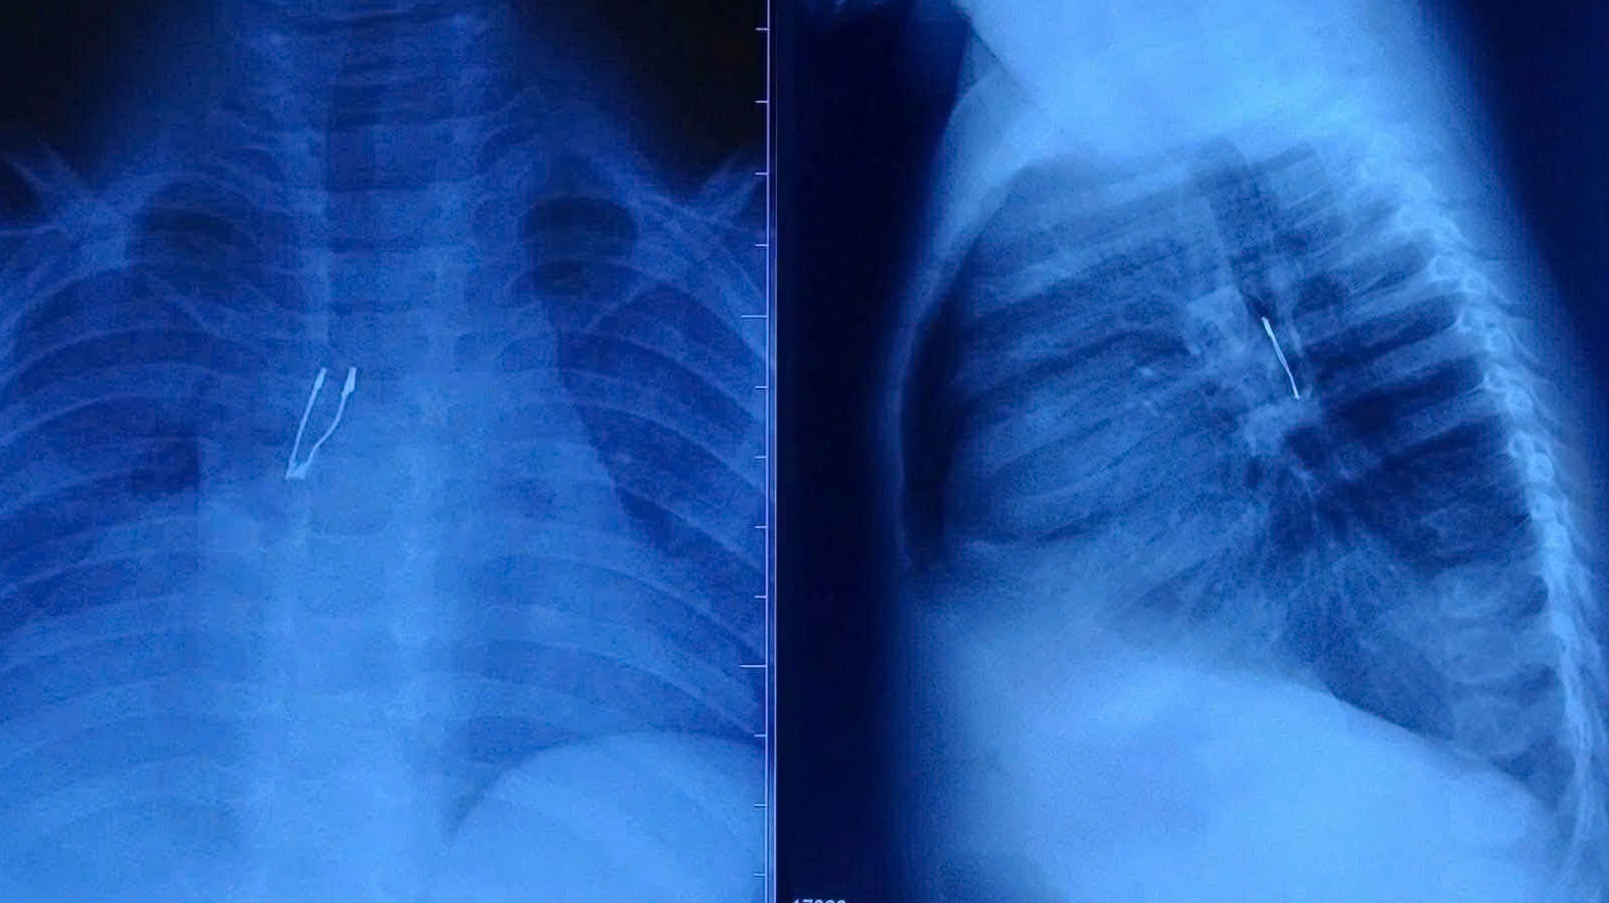

Tại Bệnh viện Nhi đồng 1, kết quả chẩn đoán cho thấy dị vật cản quang nằm ở phế quản gốc phải, kèm dấu hiệu xẹp phổi phải chưa hoàn toàn và tràn khí trung thất – những biến chứng tiềm ẩn nguy cơ nặng. Ngay lập tức, ê-kíp Khoa Tai Mũi Họng đã hội chẩn liên chuyên khoa, phối hợp gây mê tiến hành nội soi phế quản cấp cứu.

Hình ảnh dị vật nằm sâu trong phế quản. Ảnh: BVCC.

Dị vật được xác định là một bóng đèn LED mắc kẹt sâu trong phế quản gốc phải. Quá trình gắp gặp nhiều khó khăn do cấu trúc đuôi đèn bè, sắc nhọn, dễ gây tổn thương khi kéo qua thanh quản. Với đường thở của trẻ còn rất nhỏ, bác sĩ phải xoay chỉnh dị vật từng chút một để đưa phần đầu ra trước, hạn chế tối đa nguy cơ trầy xước hoặc rách niêm mạc.